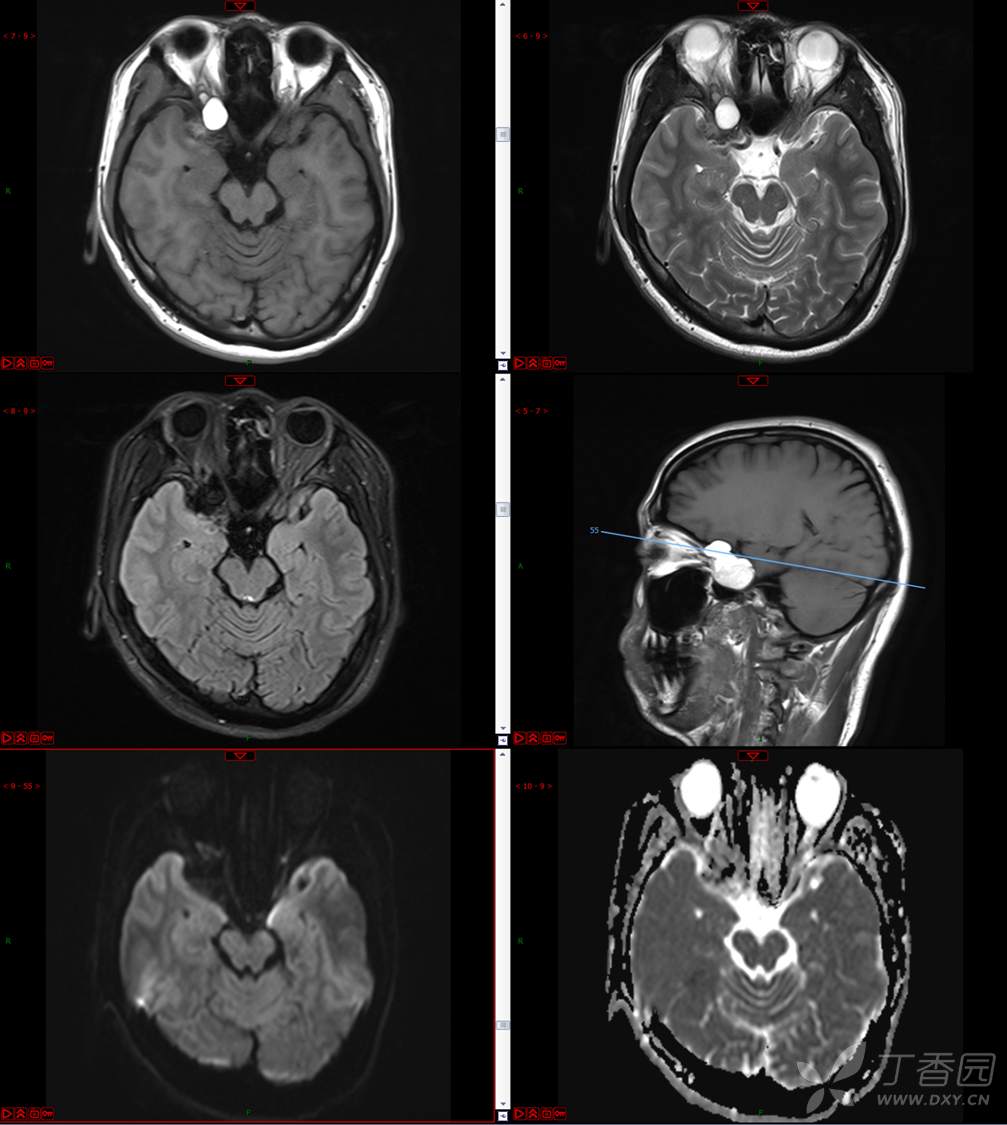

【影诊笔记534】青年男性,视物模糊就诊,CT、MRI、MRS齐全,请分析~~~

主 诉:视物重影5天。

现病史:患者5天前无明显诱因出现视物重影,表现为右视时视物成双,无头痛、头晕,无恶心、呕吐,无面部麻木、饮水呛咳等,于当地医院就诊,行颅脑MR示“颅内占位性病变”,现为求进一步治疗来诊。患者病来精神可,饮食、睡眠正常,体重无明显变化。